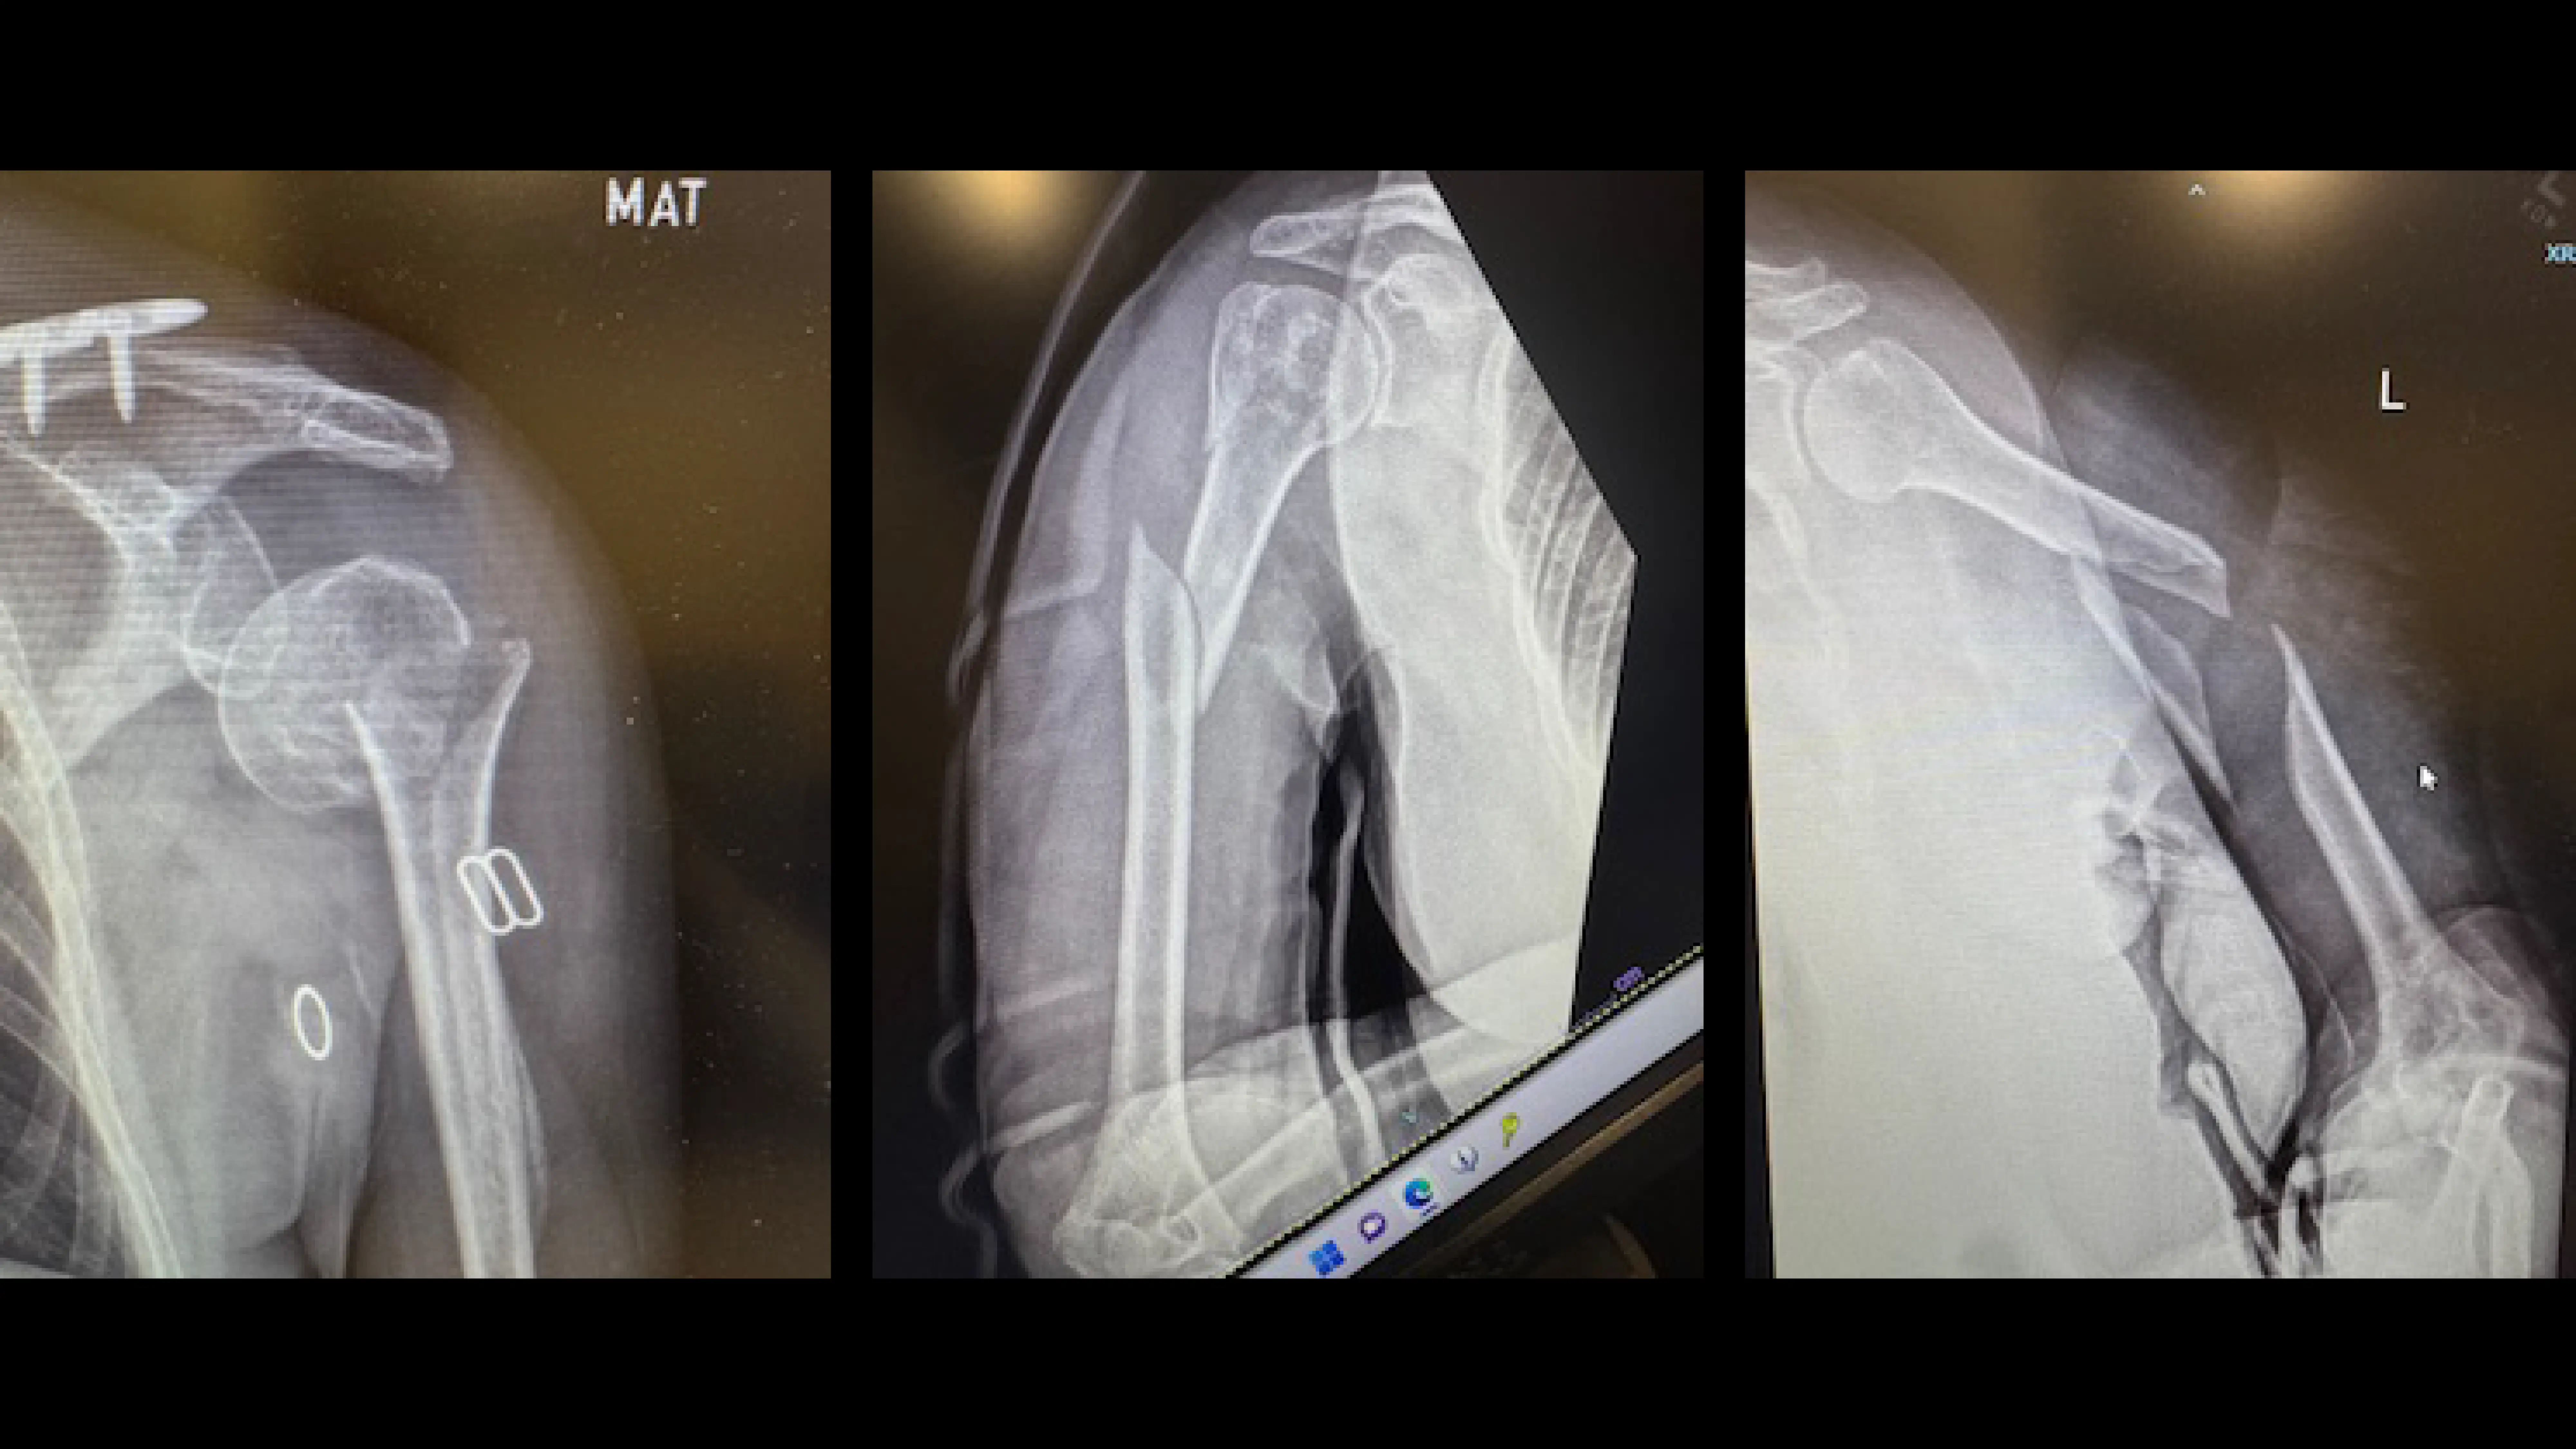

Orthopedic surgeons typically divide the humerus into three main regions, and fracture patterns vary depending on the location of the break.

Proximal Humerus Fractures (Near the Shoulder)

These fractures occur in the upper portion of the bone near the shoulder joint and are common in older adults, often occurring after a fall onto an outstretched arm.

These injuries are commonly described using the Neer classification system, which is based on the number of displaced bone fragments (or “parts”).

Humeral Shaft Fractures (Mid-Arm)

Humeral shaft fractures occur in the middle portion of the upper arm bone and are often caused by direct trauma, falls, or high-energy injuries such as motor vehicle accidents.

Open Reduction and Internal Fixation (ORIF)

ORIF is commonly used for proximal humerus fractures and humeral shaft fractures.

During this procedure:

• The surgeon makes an incision to directly visualize the fracture

• Bone fragments are realigned

• Plates and screws are used to hold the bone in position while it heals

Intramedullary Nailing (IMN)

Intramedullary nailing is frequently used for humeral shaft fractures.

A metal rod (nail) is inserted into the central canal of the humerus, spanning the fracture. Locking screws are placed at both ends of the rod to prevent rotation or shortening of the bone.